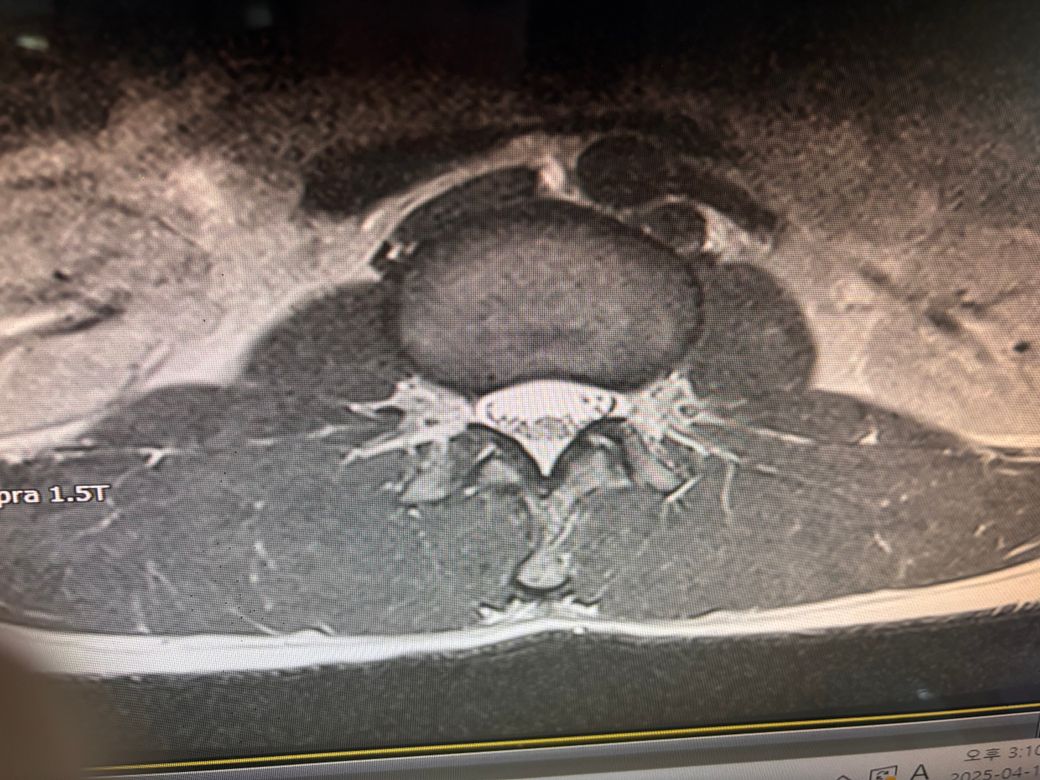

mri상 디스크나 신경에 문제가 있나요?

다리에 피가 안통하는 것 같은 느낌이 생긴지

좀 되었는데 이 사진에 나와있는 mri에서 디스크나

허리 신경에 문제가 있는 부분이 있는 궁금합니다

말씀하신 내용 토대로 답변 드리자면 일반적으로 다리에 혈액이 안 통하는 듯한 느낌, 저림, 무감각, 쑤심 등의 증상이 있다면 허리(요추) 디스크나 신경 압박 가능성을 먼저 의심해볼 수 있습니다. 특히 요추 4-5번(L4-L5), 요추 5번-천추 1번(L5-S1) 부위에서 디스크 탈출이나 협착이 있을 경우 좌골신경통처럼 다리까지 영향을 줄 수 있어요.

만약 MRI에서 디스크가 돌출되어 신경근을 압박하거나 척추관이 좁아진 소견을 보였다면, 현재 증상과 관련이 있을 가능성이 높습니다.